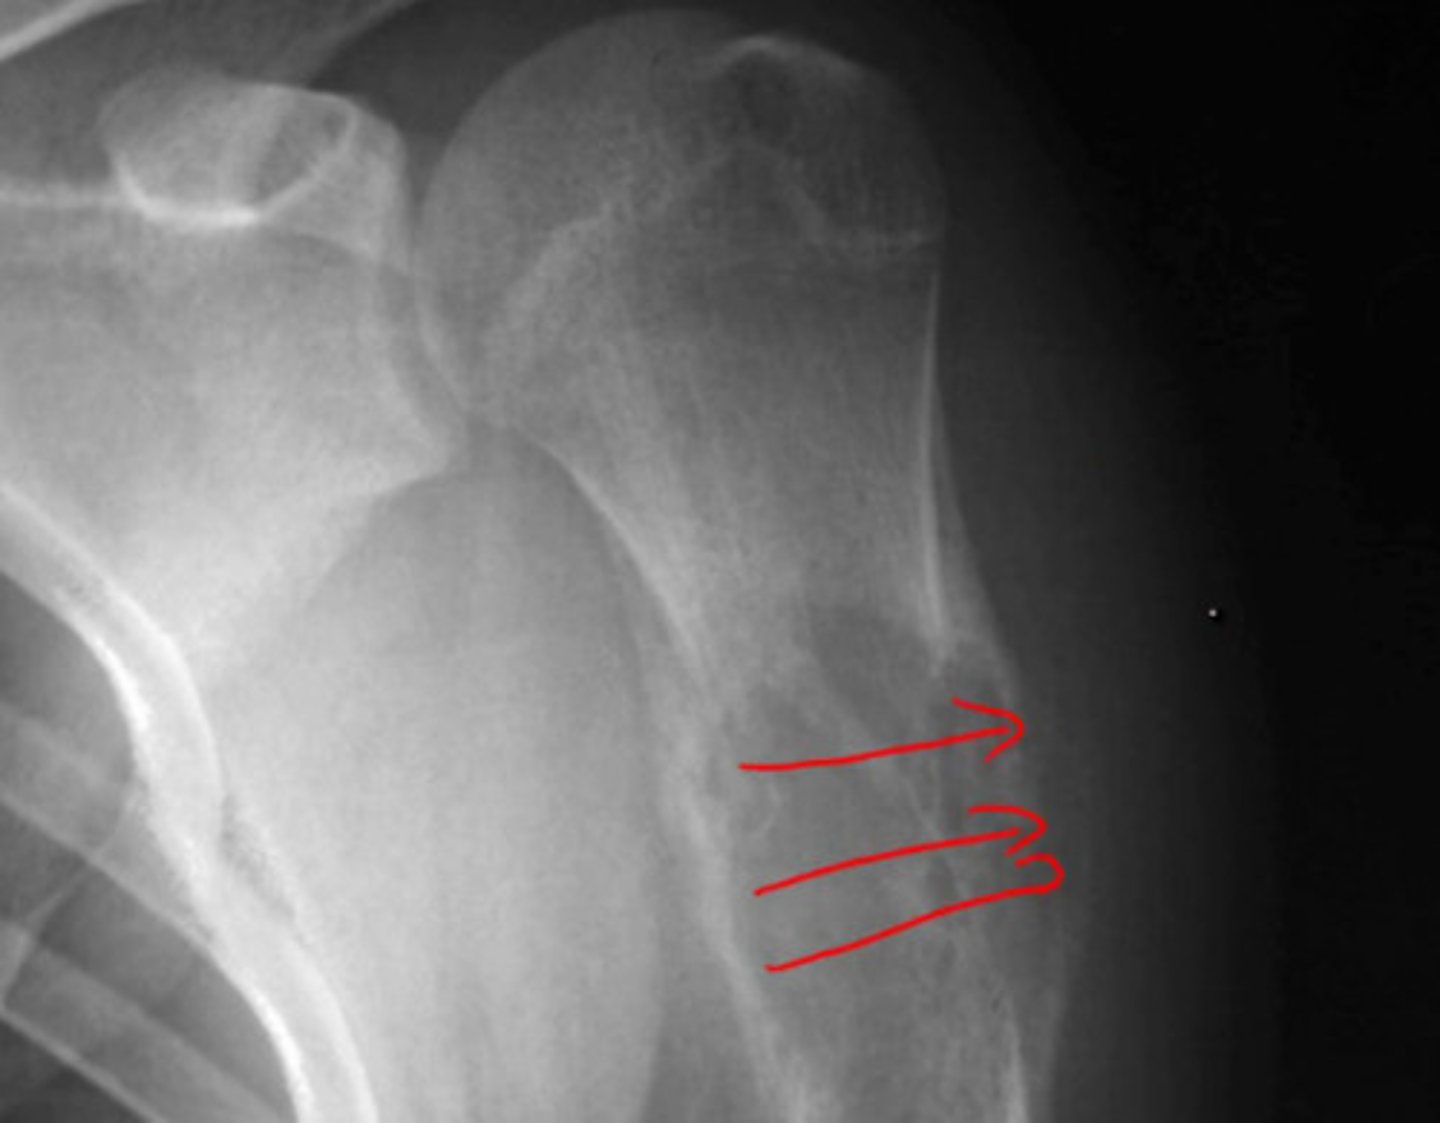

__ is the most common primary bone tumor in children and young adults involves metaphysis of long bones.

Osteosarcoma

- large and tender mass

- sunburts poeriosteal rxn + Codman triangle